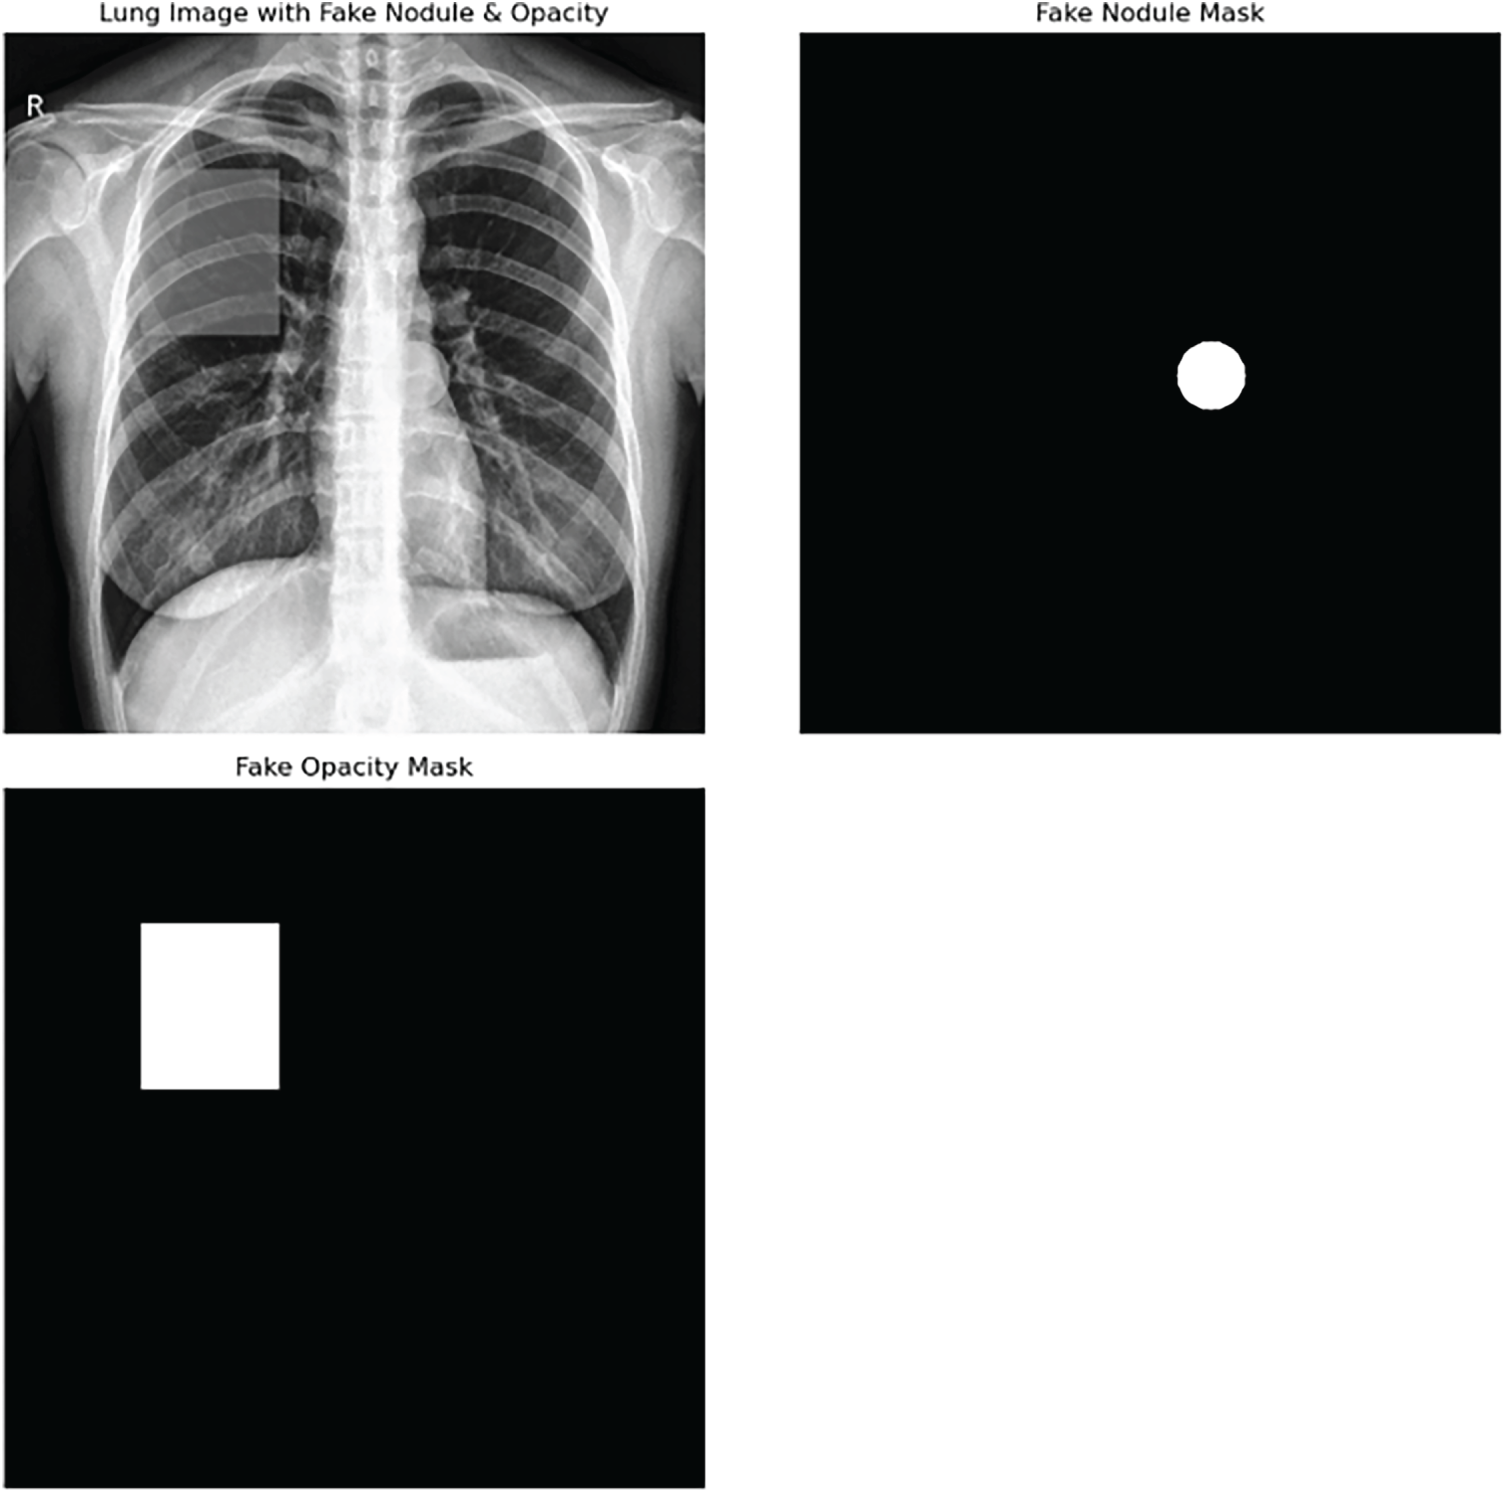

In this paper, data preparation was instrumental to the overall success and effectiveness of the detective framework of reflections from a generative adversarial network (GAN) presented. At first, the databank was put together using publicly accessible medical imaging repositories that offered a variety of imaging techniques, among them MRI [22], CT [23], X-ray [24], and fundus photographs [25]. The dataset consisted of 10,000 images in total, and the distribution that followed was observed: 2500 MRI images, 2500 CT images, 2500 X-rays, and 2500 fundus images. After that, real images were altered systematically through the use of different GAN architectures like CycleGAN, StyleGAN, and Pix2Pix models so as to impersonate real-world adversarial attacks. The goal of the synthetic manipulations was to impose a variety of artifacts so that the artificial lesions, color aberrations, texture hallucinations, and soft geometric deformations that were used to simulate pathological features without imposing visually salient artifacts could be recognized by the model. This helped machine learning to become well-trained under potential real-world attack scenarios by providing a balanced dataset consisting of 5000 real images and 5000 images manipulated by the GAN. Both the original and GAN-corrected images were downscaled to a consistent 224 × 224-pixel resolution across all modalities and to be optimally compatible with the ResNet18 architecture used for the extraction of high-level features. Pixel intensity was also normalized to the range [0, 1] so that neural network training would converge stably and differences in intensity scales arising from different imaging devices and acquisition protocols could be minimized. Besides this, every image was provided with a label indicating whether it was a real one or a GAN-generated one, thus enabling supervised learning. The entire dataset was randomly divided into training, validation, and testing sets in the ratio of 70:15:15, respectively, and there was class balancing within each split. Consequently, the training set consisted of 7000 images (3500 real and 3500 GAN-altered), the validation set consisted of 1500 images (750 real and 750 GAN-altered), and the test set consisted of 1500 images (750 real and 750 GAN-altered). This thorough data preparation step was crucial to ensuring that the model would be exposed to a wide range of possible GAN-induced alterations, thus allowing the development of a robust detector that could distinguish between true medical images and those subtly manipulated by generative models. Sample normal images are shown in Fig. 2, and samples of GAN-generated fake hallucinations are shown in Figs. 3–5. The dataset was characterized by a moderate degree of class imbalance between real and GAN-generated medical images. To solve this problem, we took steps at both the data and the loss-weighting levels. Samples of the minority class were subjected to random oversampling and geometric and intensity-based transformations (e.g., rotations, flips, brightness adjustments) for augmentation in order to increase feature diversity. Moreover, the cross-entropy loss with class weights was implemented to misclassify underrepresented classes and thus penalize them more seriously. These combined measures ensured that the model maintained balanced learning behavior and improved generalization across modalities.

Figure 5: GANs generated fake hallucinations on lungs x-ray images.